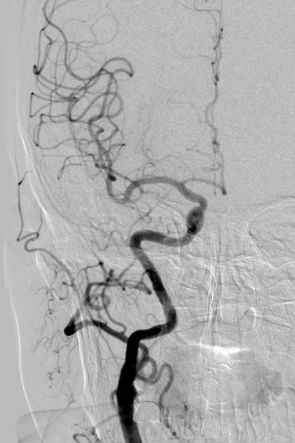

入院后行全脑血管造影证实右侧颈内动脉眼段动脉瘤。瘤颈宽约4.91mm,瘤体最大径约8.21mm,载瘤动脉远近端血管直径分别为3.07mm、3.52mm。

术前造影:

正侧位造影示动脉瘤内造影剂明显滞留,载瘤动脉通畅,血流导向作用显著。